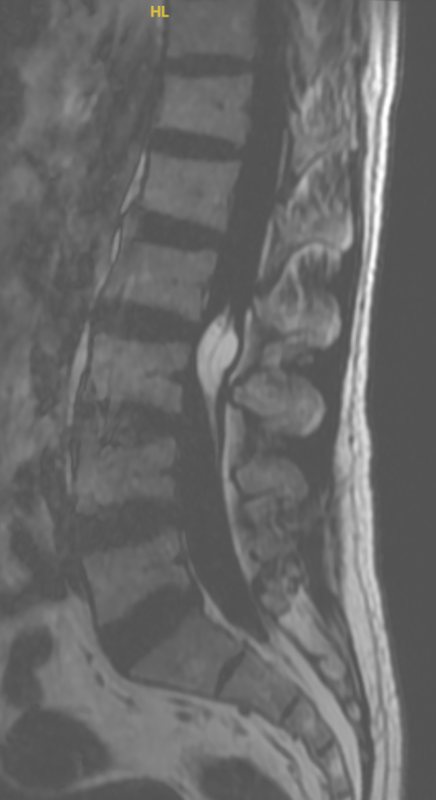

腰椎終絲脂肪瘤

最近收治一位腰椎的終絲脂肪瘤病人,40多歲男性,因腰部下肢放射性疼痛起病,行腰椎磁共振提示腰椎脂肪瘤,行手術(shù)切除。期待良好預(yù)后。什么是終絲脂肪瘤?終絲脂肪瘤(filarlipoma)是指在連接脊髓末端的終絲內(nèi)出現(xiàn)的良性脂肪組織團(tuán)塊,屬于先天性發(fā)育異常。臨床特點(diǎn)多為偶發(fā)影像學(xué)發(fā)現(xiàn):>95%的患者在腰椎MRI中被意外發(fā)現(xiàn),無(wú)任何癥狀。少數(shù)出現(xiàn)牽拉癥狀:約5%患者因脂肪瘤牽拉導(dǎo)致下肢疼痛、麻木、排尿排便障礙等“牽拉性脊髓綜合征”(TCS)表現(xiàn)。影像學(xué)診斷MRI上脂肪瘤在T1、T2序列均呈高信號(hào),可通過(guò)脂肪抑制序列進(jìn)一步確認(rèn)。治療與隨訪無(wú)癥狀者:定期隨訪觀察,無(wú)需干預(yù)。出現(xiàn)TCS癥狀者:建議行顯微或微創(chuàng)手術(shù)切斷終絲并切除脂肪瘤,術(shù)后大多數(shù)癥狀可緩解,預(yù)后良好。